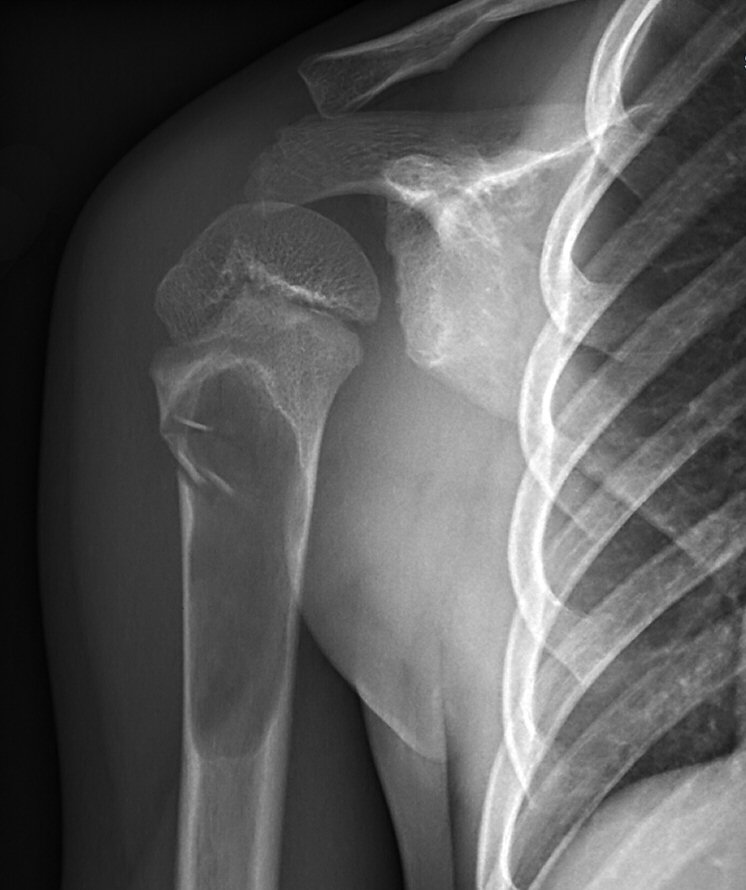

Aneurysmal bencysta lateralt i nyckelben